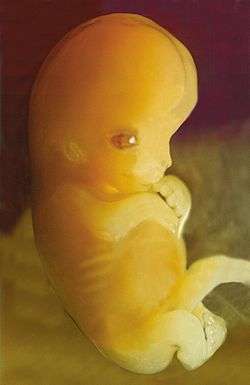

A human embryo, seven weeks old or from the ninth week of pregnancy. | |